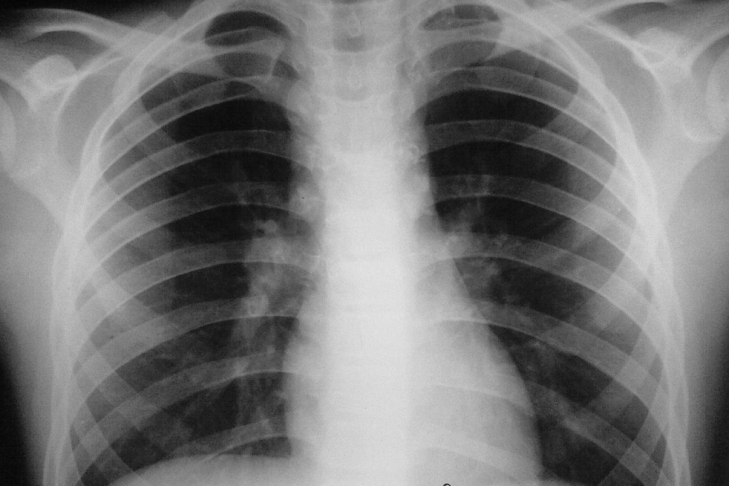

Всемирная организация здравоохранения (ВОЗ) выступила с официальным предупреждением относительно зашкаливающего числа больных туберкулезом в России и Республике Беларусь. По мнению международных экспертов, это угрожает всей Западной Европе. Значительный вклад в статистику вносят мигранты из бывших союзных республик. Именно они могу завезти инфекцию.

К счастью, Россия и Беларусь не стоят на первом месте в рейтинге стран с туберкулезом. Самая критическая ситуация зафиксирована в Китае, Индии и Южной Африке. По общим подсчетам, пишет The Moscow Times, в 2012 году туберкулез развился у 8,6 миллиона человек. 1,3 миллиона скончались. 450000 случаев связаны с особо стойким штаммом туберкулеза. К 2015 году до 2 миллионов человек могут столкнуться с резистентным туберкулезом.

ВОЗ призывает уменьшить уровень инфицированности. Так, к 2035 году желательно сократить количество новых зараженных до уровня менее 10 новых случаев туберкулеза на миллион человек в год. А к 2050 году эксперты хотят вообще избавиться от инфекции. Предложенная стратегия касается 33 стран. 21 страна находится в Европе. И здесь уже снижены показатели инфекции. Основными жертвами туберкулеза становятся мигранты, малообеспеченные, заключенные, наркоманы, алкоголики, ВИЧ-инфицированные, лица без определенного места жительства. У них туберкулез может развиваться в скрытой форме годами.